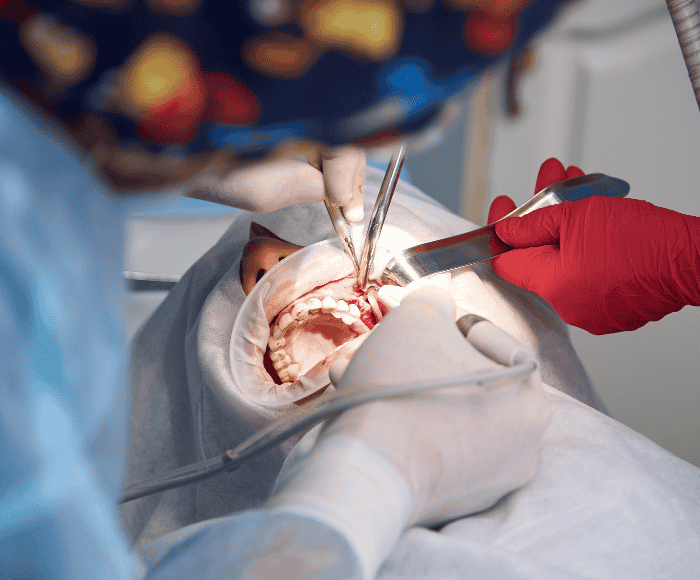

We maintain strict hygiene standards, use modern dental equipment, and follow proven clinical procedures for accurate diagnosis and long-lasting results. From routine check-ups to advanced dental treatments, our clinic is fully equipped to deliver complete oral health solutions under one roof.